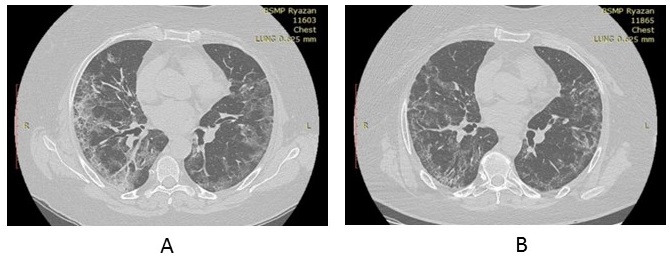

Repeated X-ray CT of lungs (18th day of illness, in hospital): in the central and peripheral areas of lungs on both sides, extended areas of consolidation of ground-glass opacity type of irregular shape with sharp slightly cord-like contours with emphaticalness of the intralobular interstitium in the lower lobes. The volume of involved lung parenchyma of the right lung — up to 40%, of the left lung — up to 35% (Figure 3A).

Fig. 3. Dynamics of changes of the results of X-ray computed tomography of lungs of patient R., 61 years old, with COVID-19, in the course of complex treatment including bovhyaluronidase azoximer: in the hospital on admission (18th day of illness, before start of therapy with bovhyaluronidase azoximer) (A), 27th day of illness (10th day of treatment with bovhyaluronidase azoximer) (B).

Therapy was given: dexamethasone intravenously, baricitinib, enoxaparin subcutaneously, bovhyaluronidase azoximer intramuscularly once every 3 days from the 18th day of the disease. In the course of therapy, the content of lymphocytes in peripheral blood was 1.0 x 109/l, CRP ― 10 mg/l, ferritin ― 320 µg/l, fibrinogen ― 365 mg%. Before treatment with bovhyaluronidase azoximer, SpO2 without oxygen insufflation was 90%, after the 2nd injection of SpO2 ― 93% without oxygen therapy.

X-ray CT of lungs in dynamics after 10 days (between two X-ray examinations, 3 injections of bovhyaluronidase azoximer were made as part of complex therapy): extended areas of consolidation of ground-glass opacity type of irregular shape with sharp slightly cord-like contours, evident intralobular interstitium in the lower lobes earlier observed in the central and peripheral areas of both lungs, restructured to smaller areas of cord-like consolidation and reticulation. The volume of the involved parenchyma of the right lung was up to 15%, of the left lung — to 10% (Figure 3B).

Thus, the dynamics of SpO2, X-ray CT changes of lungs in the course of complex therapy with bovhyaluronidase azoximer evidences not only the effect of the drug on the post-inflammatory pneumofibrosis, but also its potential ability to degrade hyaluronan that accumulates in the lung tissue in the earlier stages of the inflammatory process.